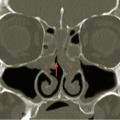

Polypose nasosinusienne

La polypose nasosinusienne est une rhinosinusite diffuse caractérisée par la présence de polypes bilatéraux dans les cavités nasales venant du massif ethmoïdal. Sa physiopathologie repose sur une inflammation chronique de la muqueuse des cavités nasales et sinusiennes marquée par une infiltration éosinophilique plus ou moins…

Tableaux et figures